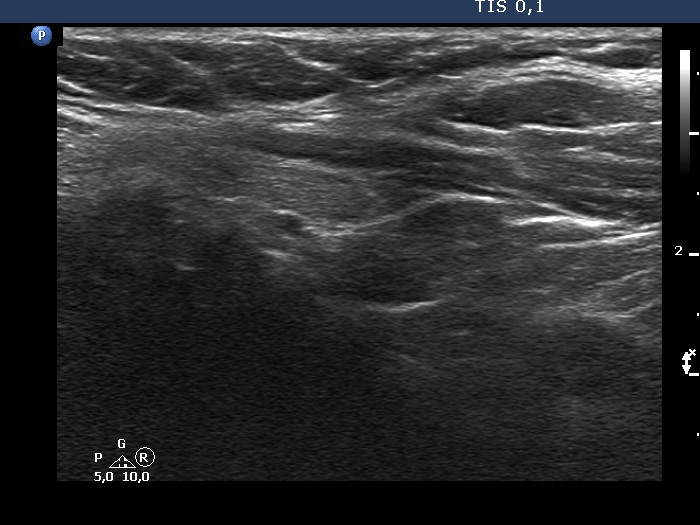

Lower part of the left lobe, another longitudinal scan - bit lower than the previous image. The nodule is more elongated and its lower pole is much less evident.